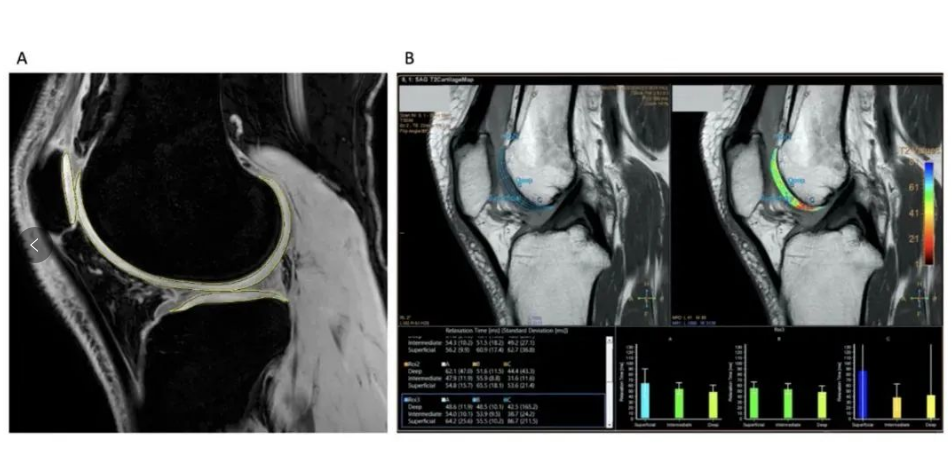

结果显示:全程未出现严重不良反应事件,而无论是高剂量还是低剂量,MSCs的治疗效果均优于安慰剂组,患者中有75%报告疼痛减轻与功能改善,达到了疗效终点。 在疾病改善定量评估中,该疗法也在改善软骨体积和质量方面显示出积极的作用。综合来看,或提示MSCs疗法有延迟或预防TKR手术(人工全膝置换术)的潜能。

△定量MRI分析软骨变化